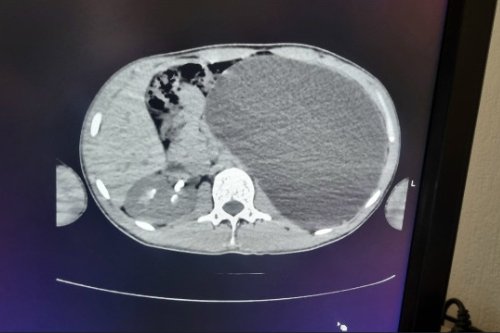

Парень проходил УЗИ по направлению компании, в которую он пытался трудоустроиться. Медики обнаружили объемное образование в брюшной полости, а именно расширение полости почки. В любую секунду орган мог разорваться.

— У нашего пациента почка достигла размеров пятилитровой бутылки! Она занимала почти весь объем живота и давила на все соседние органы. Это была настоящая «бомба замедленного действия»: любая травма, случайный удар в живот – и мешок мог разорваться внутри, – рассказали в ДГКБ № 1.